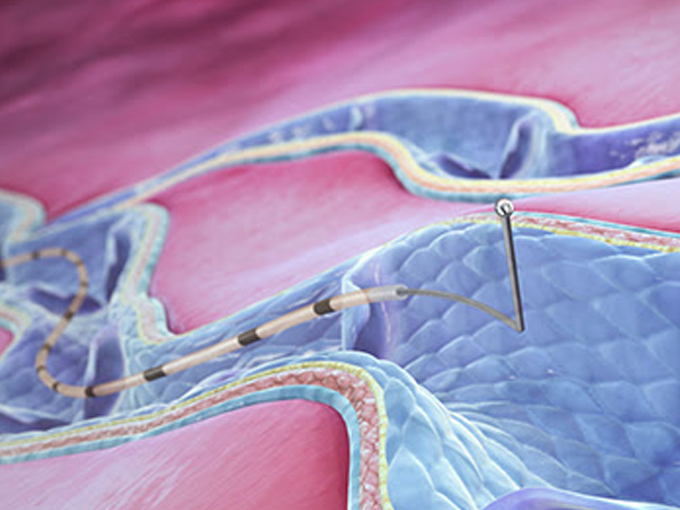

하지정맥류 고주파 열폐쇄술로써 비교적 낮은 온도(120도)로

혈관 주변의 정상조직 손상을 최소화 하면서 병든 혈관만을 치료합니다.

3세대 치료법인 클라리베인을 이용한 기계적, 화학적 치료도 가능합니다.

열손상으로 인한 부작용 및 합병증이 거의 없습니다.